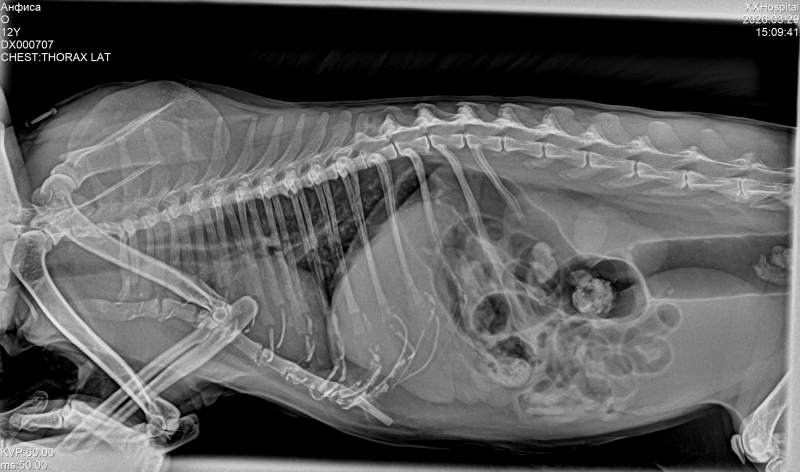

Кошку свозили. Склероз почек. В левой нарушен кровоток. Креатинин удалось нам снизить, стал в пределах нормы, но высокий. Мочевина так и осталась 22, при норме 12. Рентген лёгких без отека, такой же, как был но расширение желудка сильное. Нужно нормальную диету ренальную. Позже прикреплю обследование. Сегодня вышло 6800 р. Долг клинике 8900р. Нужно кошке снизить мочевину, надо капать внутривенно 10 часов на стационаре. Стоить будет 2800 р.

В связи с возрастом почки у кошки ухудшились, предпосылки уже в прошлом были и по УЗИ почек. По уровню мочевины.

Сейчас задача снизить мочевину- она в 2 раза выше нормы. Креатинин за неделю чуть удалось снизить- я ее выпаиваю дополнительно и увеличила дозу ипакитине.

Возрастная кошка с воспалением- и почки уехали, и ринит, и бронхит никуда не делся - жёсткое дыхание, а рентен, что в январе, что в марте- после 21 дня антибиотика- одинаковый. Плюс пневмофиброз... Еще и почки поехали. Еще в ноябре мочевина и креатинин были в норме. А сейчас шкалит. Но пока мы не улучшим креатинин и мочевину-нельзя снова пичкать антибиотики-разрушать почечную ткань.. а надо- что-то делать, чтоб убирать воспалительный процесс. А если не убирать воспаление - портятся почки. Вот такой замкнутый круг.